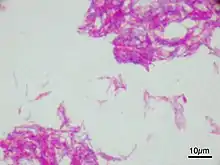

Infection

Infection with Schistosoma haematobium (bilharzia or schistosomiasis) may cause bladder cancer, particularly of the squamous cell type.[29] Schistosoma eggs induces a chronic inflammatory state in the bladder wall resulting in tissue fibrosis.[30] Higher levels of N-nitroso compounds has been detected in urine samples of people with schistosomiasis.[31] N-Nitroso compounds have been implicated in the pathogenesis of schistosomiasis related bladder cancer. They cause alkylation DNA damage, specially Guanine to Adenine transition mutations in the HRAS and p53 tumor suppressor gene.[32] Mutations of p53 are detected in 73% of the tumors, BCL-2 mutations accounting for 32% and the combination of the two accounting for 13%.[33] Other causes of squamous cell carcinoma of the bladder include chronic catheterizations in people with a spinal cord injury and history of treatment with cyclophosphamide.[34][35]